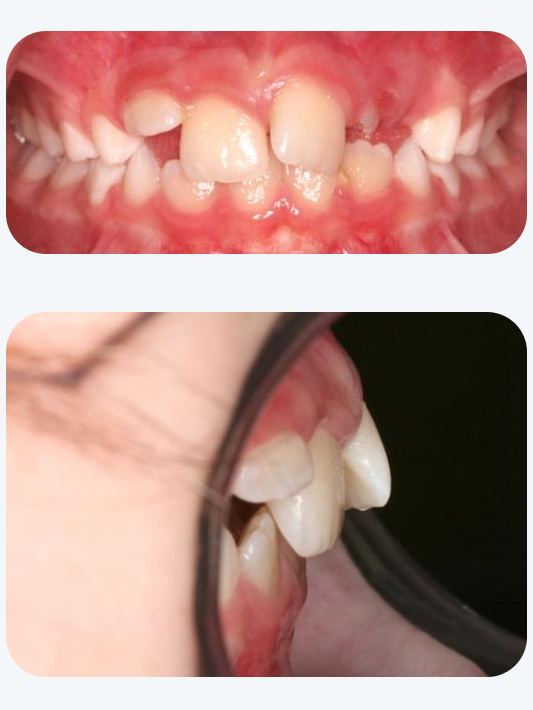

マイオブレース治療を行った症例

治療前

治療後

12歳 男子

主訴:歯並びがデコボコ

治療期間:12か月

治療経過:マイオブレース治療と筋機能療法を行った。月に1度来院していただき、お口の中やトレーニング状況を確認。

費用:40万円(税別)

※マイオブレース治療は4~5歳から開始するのがお勧めですが、上記の症例のように年齢が上がっても行える場合がございます。ご相談下さい。